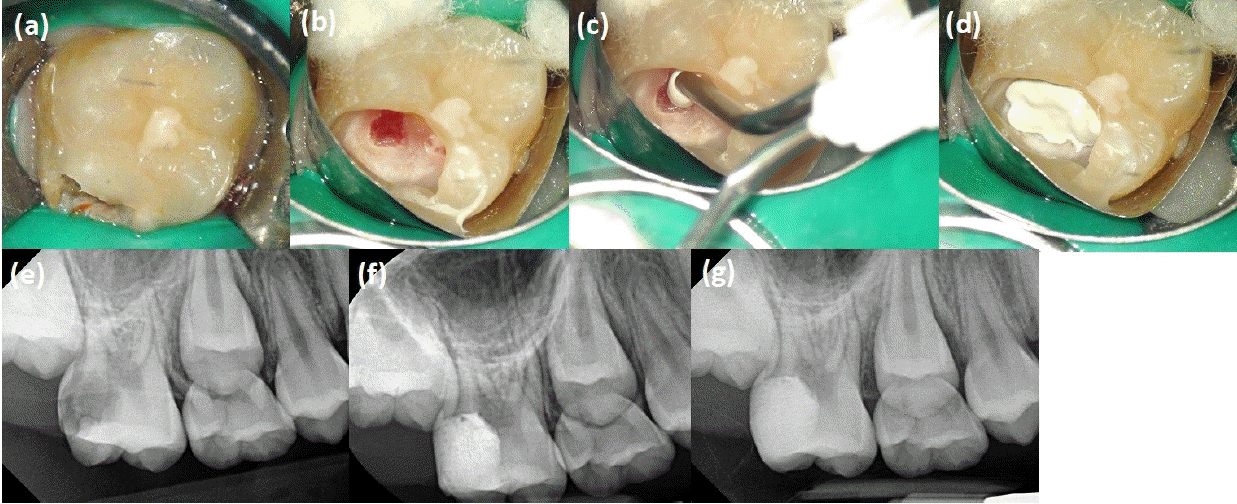

Figure 7.

Case of direct pulp capping on the left maxillary first molar in an 11-year-old male patient who was recommended for extraction. The goal of treatment was to preserve the coronal space of tooth #26 until tooth #27 erupted. Considering the tooth structure and the patient’s cooperation, post placement after root canal treatment was deferred. (a, b) Preoperative radiograph and clinical image. (c) Due to insufficient distal tooth structure, a thin glass ionomer wall was built first to aid in saliva isolation. Upon complete caries removal, the mesiobuccal pulp horn was exposed, and the pulp tissue appeared reddish and translucent in other areas. (d-f) After NaOCl disinfection, One-Fil PT (Mediclus, Cheongju, Korea) was applied using a resin instrument, spreading it widely to cover the entire pulp chamber roof. (g) Postoperative radiograph after glass ionomer restoration. An SS crown was ordered, and in the future, once the permanent dentition is fully developed, root canal treatment and post placement may be considered before final crown fabrication.